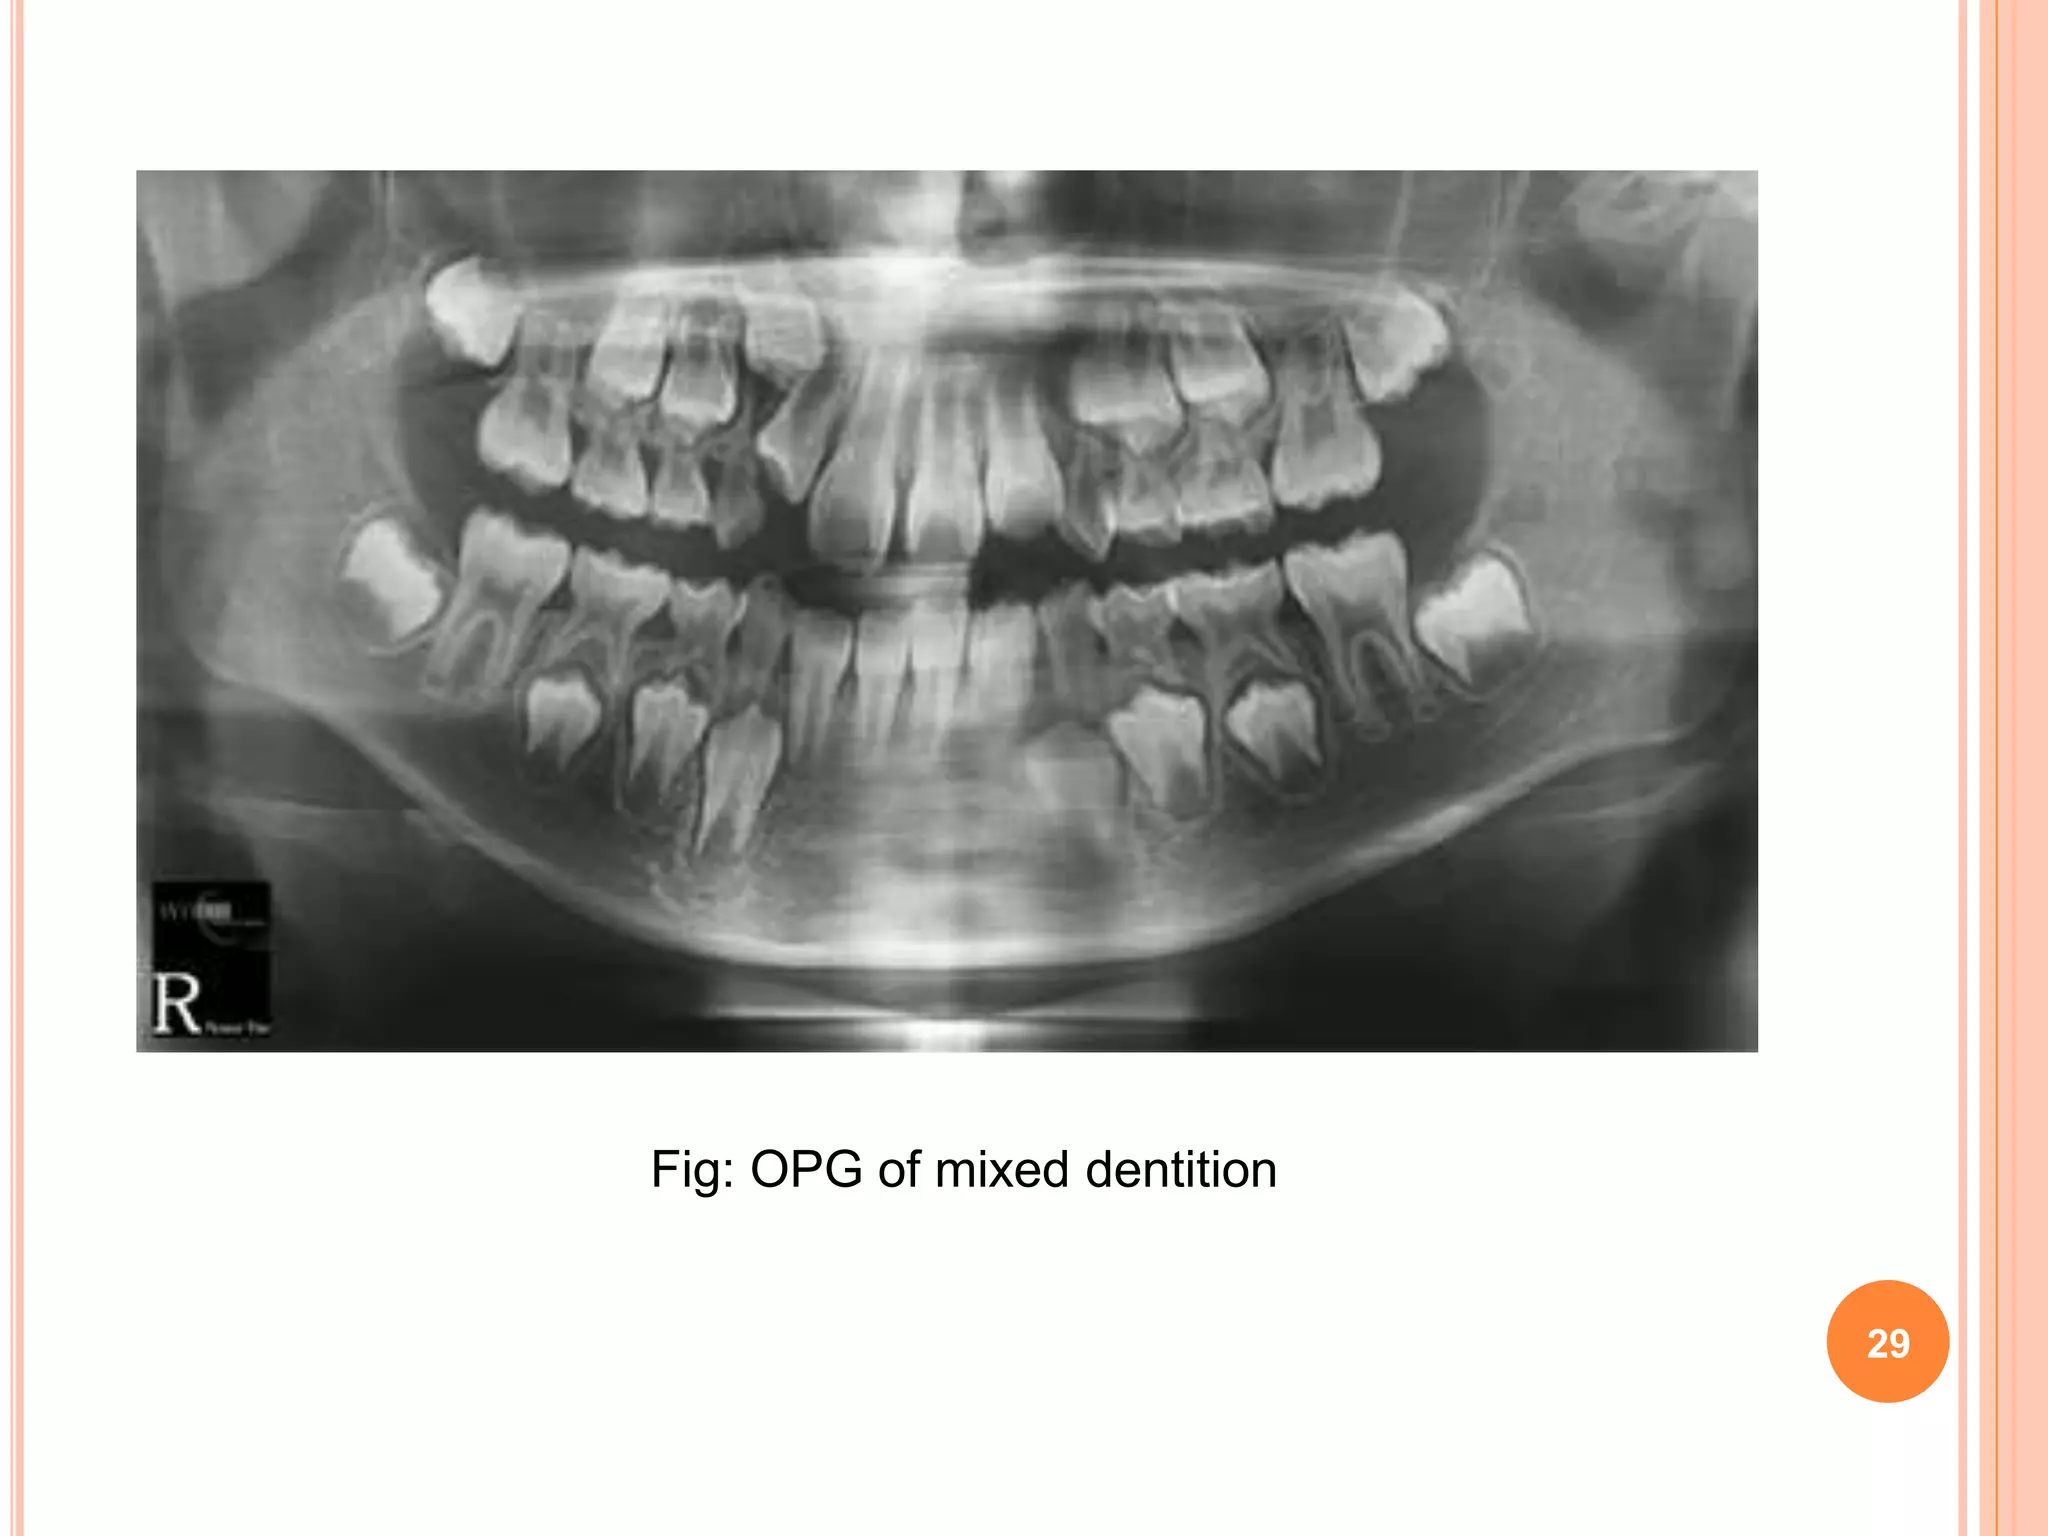

INTER-TRANSITIONAL PERIOD

 In this period the maxillary and mandibular arches

consist of sets of deciduous and permanent teeth.

 Between the permanent incisors and the first

permanent molars are the deciduous molars and

canines.

 This phase during the mixed dentition period is

relatively stable and no change occurs.

28

Fig: OPG of mixed dentition